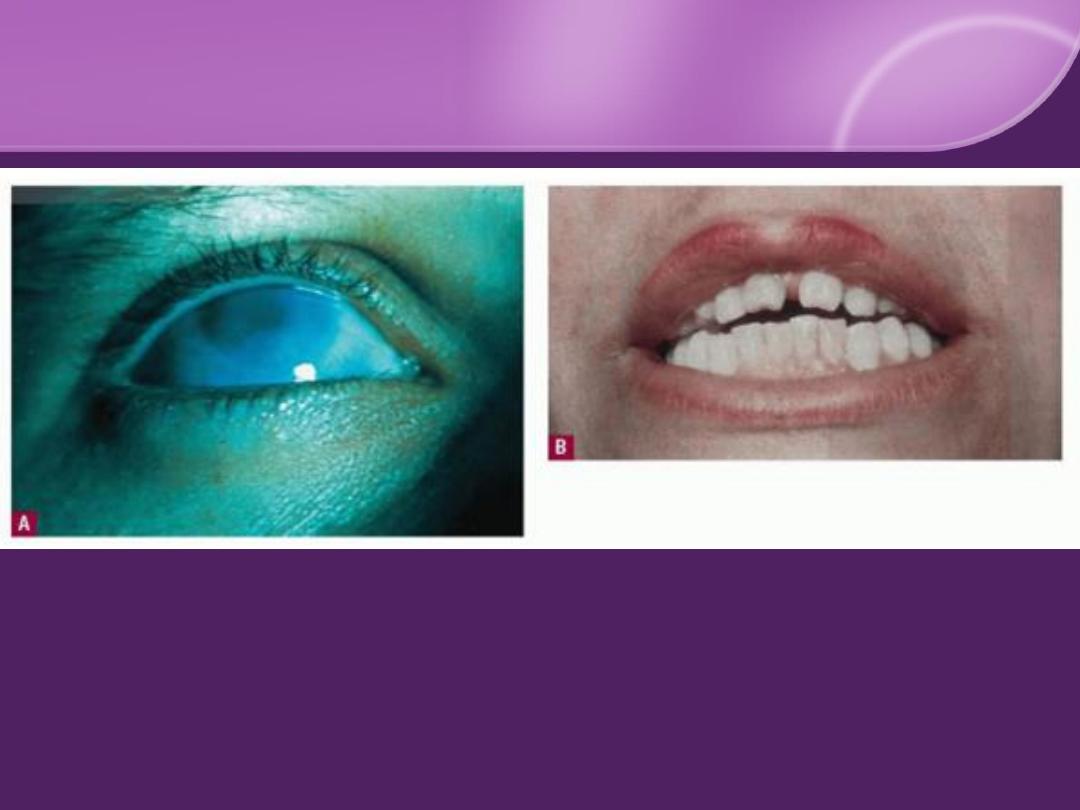

Stigmata of Congenital Syphilis

1. Ophthalmic: corneal clouding.

2. Oral: Hutchinson teeth and high-arched palate.